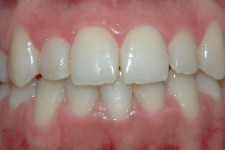

LIJEVO: 1a početno stanje,prednji zubi - DESNO: 1b nakon završetka terapijee LIJEVO: 2a revizija punjenja korijenskih kanala,višekorijenski zubi        <br />

DESNO: 2b nakon završetka terapije LIJEVO: 3a  prije revizije punjenja,jednokorijenski zub<br />